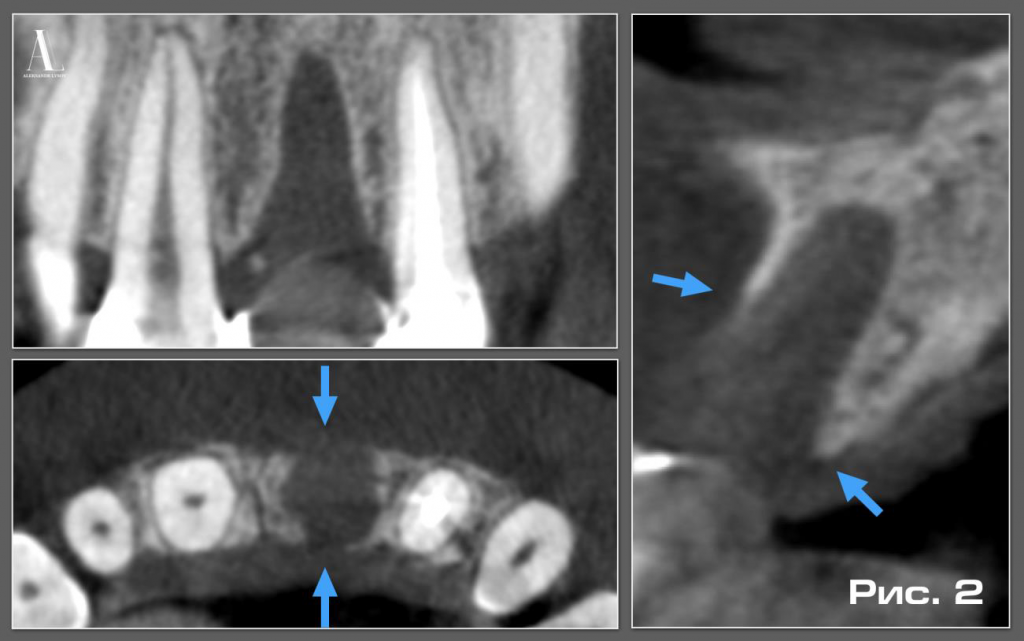

При анализе КЛКТ обнаружили костный дефект вестибулярной и небной стенок лунки 2.1 зуба. В вестибулярно-оральном направлении дефект являлся сквозным, причем вестибулярная пластинка была разрушена более чем на половину (Рис. 2).